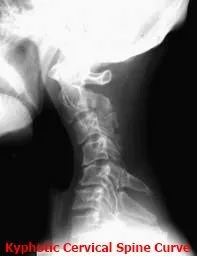

C_spine___normal.jpg This loss of normal (C-shaped forward) C_spine___kyphotic.jpg cervical curvature  is the result of the cervical acceleration/deceleration syndrome, and can be responsible for many positive orthopedic and neurological examination findings contributing to the patient’s symptomatology. X-rays cannot demonstrate microscopic tears nor show inflammation in the soft tissue (ligaments, tendons, muscle, cartilage, etc) which is one of the leading causes of the pain and soreness that one experiences following motor vehicular accident trauma. X-rays are the most cost effective study to rule out ligament insufficiency, bone pathology and vertebral misalignment leading to abnormal musculoskeletal mechanics.

• Recent epidemiological studies have shown that most injury rear impact accidents occur at crash speeds of 6 mph to 12 mph--the majority at speeds below the threshold for property damage to the vehicle. A number of risk factors in rear impact accident injury have now been verified including: rear (vs. other vector) impact, loss of cervical lordotic (C-shaped forward) curve, pre-existing degenerative changes, the use of seat belts and shoulder harness, poor head restraint geometry, non-awareness of the impending collision, female gender, and head rotation at impact.